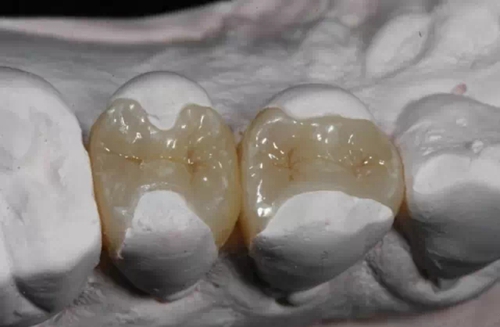

嵌體和傳統(tǒng)的補牙不同之處是,嵌體是在口外石膏模型上由專門的牙科技師制作出來的,然后再由臨床醫(yī)生將其戴入患者口內(nèi),最終粘固形成的。

嵌體的優(yōu)點就在于,它的整個的制作過程中完全避免了在口腔內(nèi)部操作的干擾因素。這就使得嵌體的制作比傳統(tǒng)的補牙要更精細。技師在制作嵌體的時候,會控制它與牙體的彌合程度,這樣就盡可能的避免了牙齒在日后的使用中再次出現(xiàn)齲壞。

嵌體的另一個優(yōu)點是,因為它的整個制作過程是在口外完成的,所以它還可以很好的恢復原來牙齒的外形,恢復原來牙齒的咀嚼效率。而這一點,是傳統(tǒng)補牙無論如何都無法比擬的